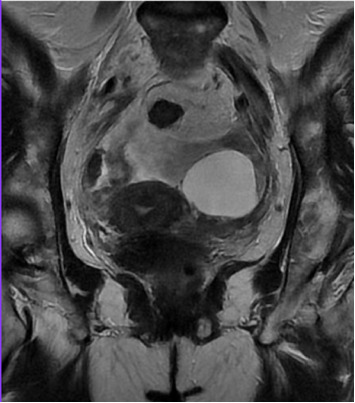

Genital tuberculosis (GT) is a rare but significant extrapulmonary tuberculosis form, often mimicking ovarian malignancy. We report a case of a 58-year-old woman with Sjögren's syndrome and rheumatoid arthritis, previously treated with infliximab, who presented with abdominal distension, weight loss, night sweats, and intermittent abdominal pain. Initial imaging and elevated CA-125 levels suggested ovarian cancer. However, intraoperative findings revealed a frozen pelvis with granulomatous inflammation, caseating granulomas, and Langhans' giant cells. Histopathological analysis and RT-PCR confirmed GT coexisting with a serous cystadenoma. GT should be considered in the differential diagnosis of pelvic masses, especially in immunocompromised patients. This case emphasizes the importance of thorough diagnostic evaluation using molecular, serological, and imaging techniques to avoid misdiagnosis and unnecessary surgical interventions. Prompt initiation of antituberculosis treatment led to significant clinical improvement. Early and accurate diagnosis of GT is crucial to prevent morbidity associated with misdiagnosis and to provide effective treatment. This case underscores the need for heightened clinical awareness and multidisciplinary approaches in managing complex cases where GT mimics malignancy, ensuring optimal patient outcomes.